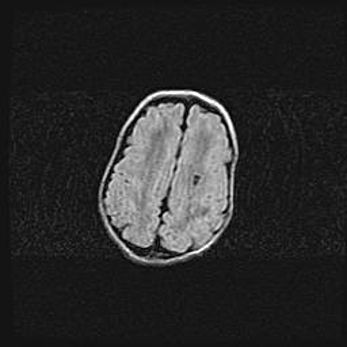

Множественные кисты обоих полушарий головного мозга, наибольшая из них в правой затылочной области. Ассиметричная атрофическая гидроцефалия.

Возраст: 7 месяцев

Вес: 5660 г

Пол: мужской

Окружность головы: 41,5 см

Срок гестации: 28-29 недель

Кисты головного мозга развиваются в результате многоочаговых некрозов вещества мозга и возникают вследствие перенесенной перинатальной инфекции, менингитов, энцефалитов, асфиксии, родовой травмы, расстройств мозгового кровообращения различного генеза. Образованию кист в веществе головного мозга плодов и новорожденных способствуют такие факторы, как высокое содержание в нем воды, недостаточная (или отсутствие) миелинизация и слабая астроглиальная реакция на повреждение.

Кисты могут сочетаться с гидроцефалией и другими поражениями головного мозга.